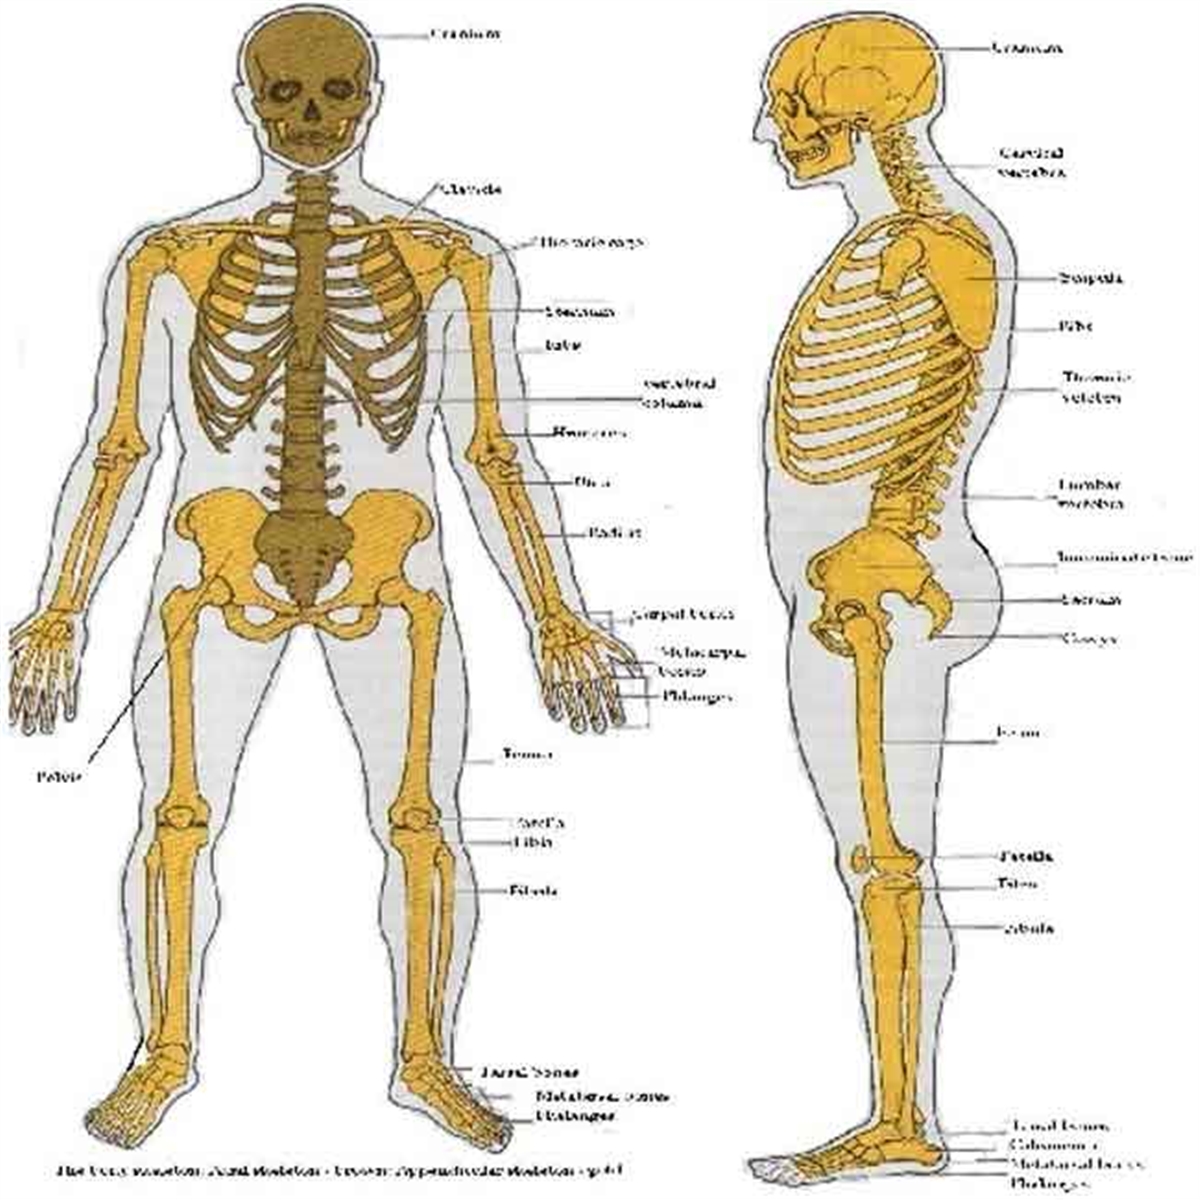

عکس اسکلت بدن انسان

عکس اسکلت بدن انسان. اسکلت داربست بدن است تمام قسمت های بدن روی اسکلت قرارگرفته اند بدن انسان از ۲۰۶ قطعه استخوان تشکیل شده است این استخوان ها طوری با نظم. هر قسمت بدن از انواع مختلف سلول تشکیل شده است. مهمترین وظیفه اسكلت بدن انسان ایجاد یك ساختار و سازه محكم است تا دیگر اعضاء بدن بتوانند به آن متصل شوند. سازه و چهارچوب اصلی بدن.

اسکلت داربست بدن است تمام قسمت های بدن روی اسکلت قرارگرفته اند بدن انسان از ۲۰۶ قطعه استخوان تشکیل شده است این استخوان ها طوری با نظم کنار هم قرار گرفته اند که انسان را قادر می سازد حرکات دقیقی داشته باشد. بدون اسكلت بدن مانند كرم شل و نرم است و این نوع شكل بندی نمیتواند. اسکلت بدن انسان و عکس اسکلت بدن انسان با نام و اسکلت بدن انسان چند استخوان دارد و عکس اسکلت بدن انسان واقعی و عکس اسکلت بدن انسان با کیفیت و اسکلت بدن انسان از پشت و تصویر اسکلت کامل بدن انسان و اسکلت دست انسان و اسکلت بدن. معرفی بدن انسان اسکلیت.

اسکلت داربست بدن است تمام قسمت های بدن روی اسکلت قرارگرفته اند بدن انسان از ۲۰۶ قطعه استخوان تشکیل شده است این استخوان ها طوری با نظم کنار هم قرار گرفته اند که انسان را قادر می سازد حرکات دقیقی داشته باشد. استخوان یک نسج بسیار محکم است زیرا در ترکیب آن منرالها مانند کلسیم و دیگر وجود. اسکلت داربست بدن است تمام قسمت های بدن روی اسکلت قرارگرفته اند بدن انسان از ۲۰۶ قطعه استخوان تشکیل شده است این استخوان ها طوری با نظم کنار هم قرار گرفته اند که انسان را قادر می سازد حرکات دقیقی داشته باشد. آناتومی سه بعدی بدن انسان عکس گرافی بدن امعاء و احشاء بدن آناتومی سه بعدی بدن انسان عکس گرافی بدن امعاء و احشاء بدن قلب کبد روده.

اسکلت داربست بدن است تمام قسمت های بدن روی اسکلت قرارگرفته اند بدن انسان از 206 قطعه استخوان تشکیل شده است این استخوان ها طوری با نظم کنار هم قرار گرفته اند که انسان را قادر می سازد حرکات دقیقی داشته باشد. اسكلت به بدن شكل میدهد. عکس اسکلت بدن انسان زن و مرد آناتومی ساتین 16 سپتامبر 2017.